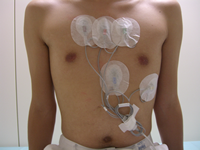

Holter 心電図(24時間心電図)

胸にシール電極をつけ、長時間の心電図記録ができる携帯用の機器で24時間連続して心電図記録を行います。

狭心症や不整脈に伴う症状がおこったときの心電図変化、薬の治療効果などを調べる検査です。